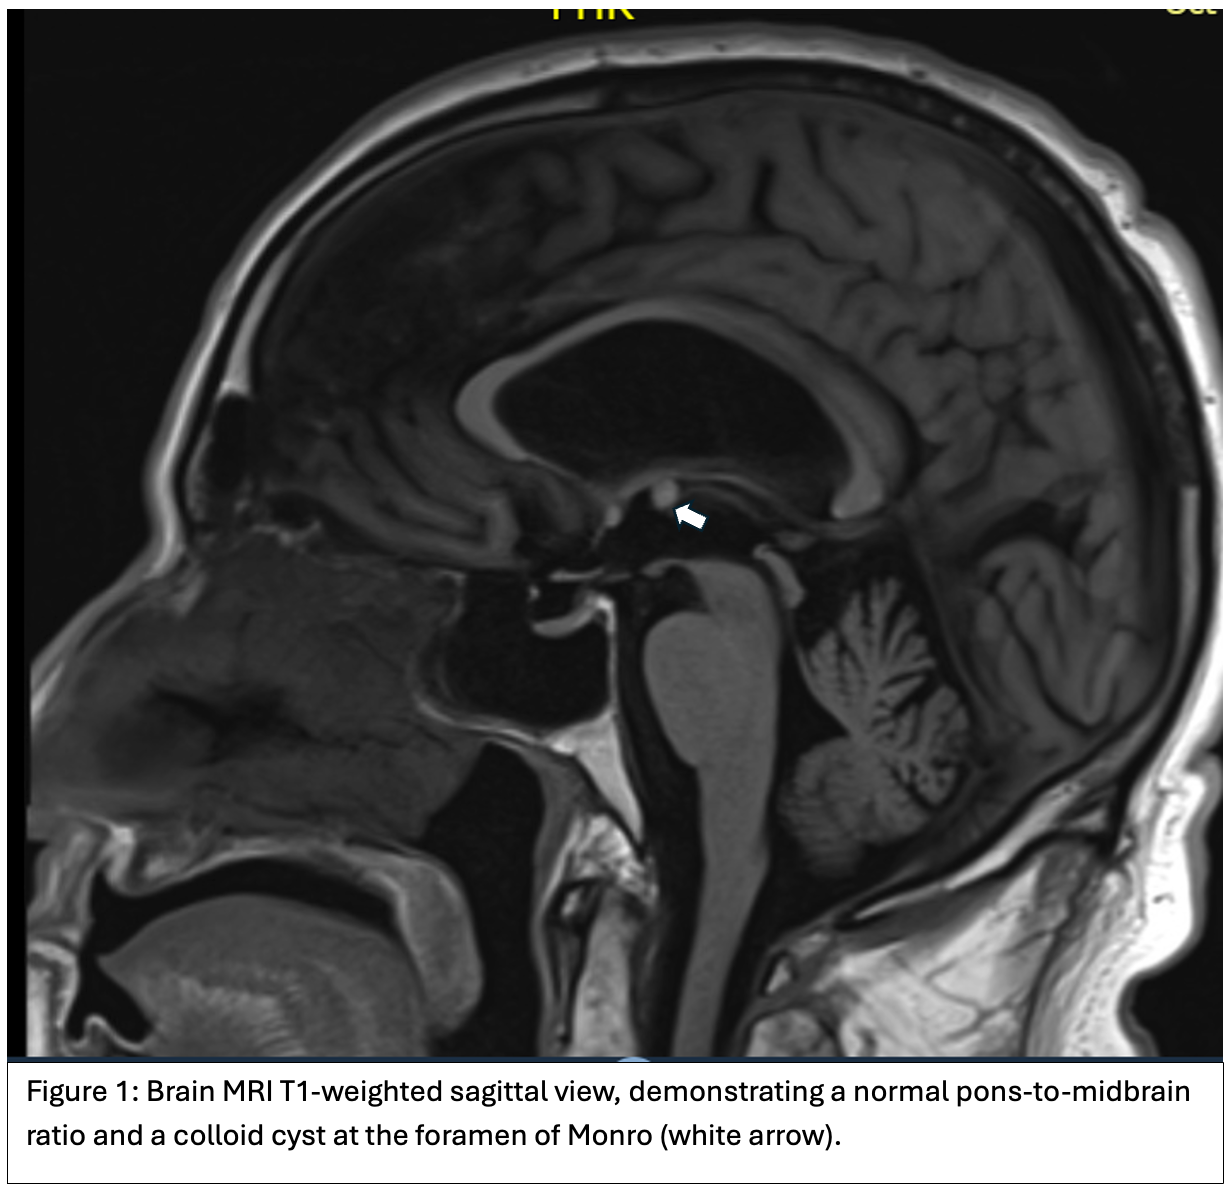

Brain MRI (Figure 1) and CT (Figure 2) showed findings consistent with NPH and a 0.6 mm colloid cyst at the foramen of Monro. The patient was treated with carbidopa/levodopa 25/100 mg, one tablet four times daily, but experienced no clinical improvement. He will be scheduled for a large-volume lumbar puncture to assess potential responsiveness to CSF drainage as a treatment for NPH.

Conclusion: This case emphasizes the difficulty of distinguishing atypical parkinsonism from secondary causes such as NPH. Despite gait impairment, oculomotor dysfunction, and levodopa unresponsiveness, the presence of NPH on MRI and a normal midbrain-to-pons ratio raise concerns for an alternative or overlapping etiology. Further evaluation via CSF drainage will help clarify the role of NPH in his symptoms and guide management.

Figure 1